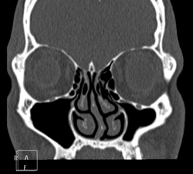

- TC Senos paranasales

Prueba radiológica que consiste en obtener imágenes de los senos paranasales de alta definición anatómica, mediante el empleo de un equipo de TC (Tomografía Computarizada). Indicaciones: cefalea, tos crónica, mucosidad, infecciones faciales.